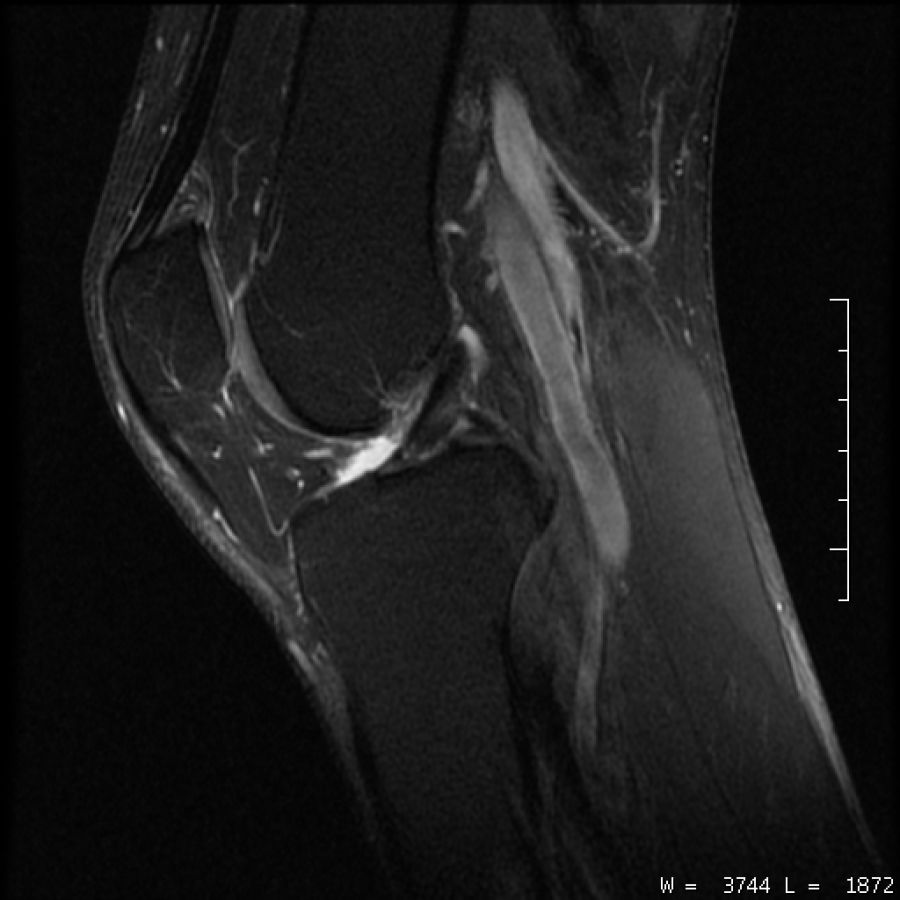

• Prothèses articulaires et IRM sur la même région ( artefacts trop important)